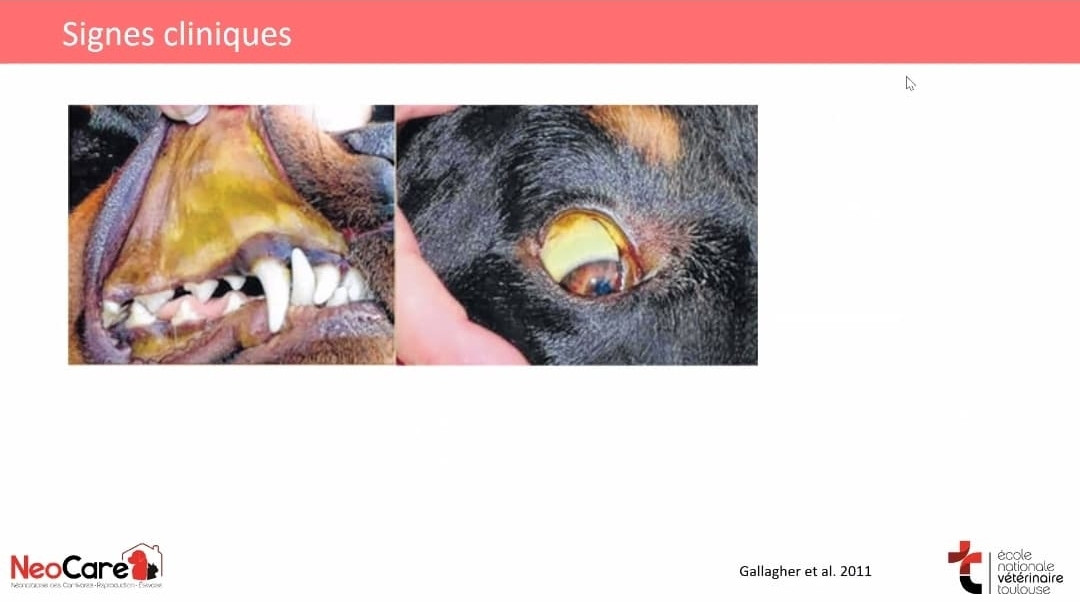

La Leptospirose Canine : Pourquoi la Vaccination est Essentielle

La Leptospirose Canine : Pourquoi la Vaccination est Essentielle

La Leptospirose Canine : Pourquoi la Vaccination est Essentielle

Les Symptômes de la Leptospirose

La Leptospirose Canine : Pourquoi la Vaccination est Essentielle

La Leptospirose Canine : Pourquoi la Vaccination est Essentielle

Les Symptômes de la Leptospirose